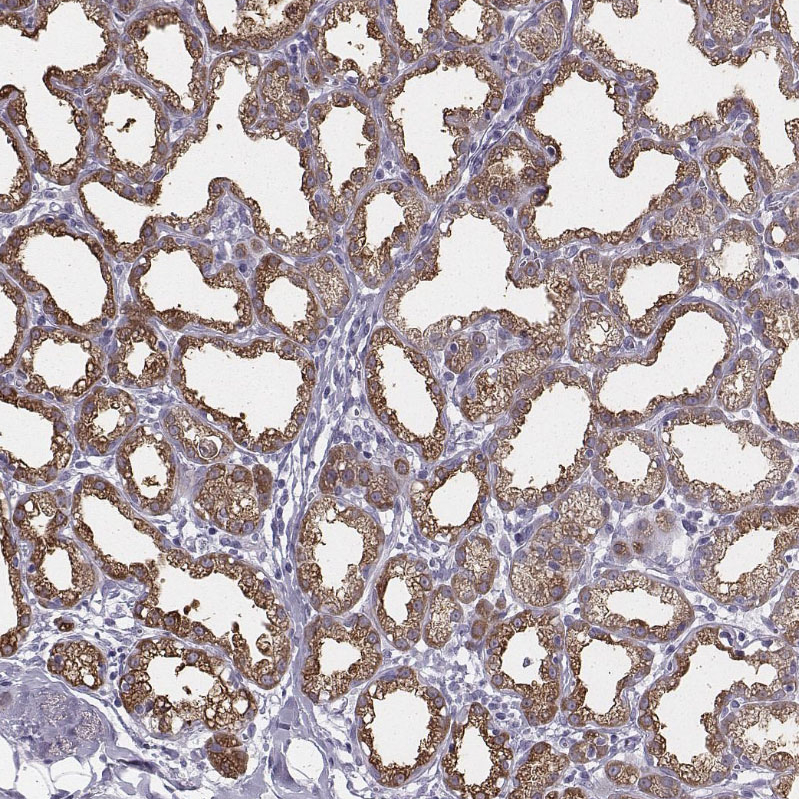

Immunohistochemical staining of human lactating breast shows moderate cytoplasmic positivity in glandular cells.